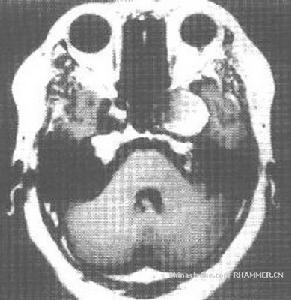

顱內占位性病變,常可通過影象學檢查獲得確診。影象學檢查包括頭顱CT掃描、核磁共振檢查及腦血管造影等。現代影象學檢查可顯示占位性病變的位置、大小、形態、數目,還能觀察到病變內部是否有囊變、壞死、鈣化、出血等。腦血管造影是根據血管的部位、形態的改變、循環時間的改變以及病理血管的出現等,間接了解病變的位置、大致形態、含血管是否豐富等。